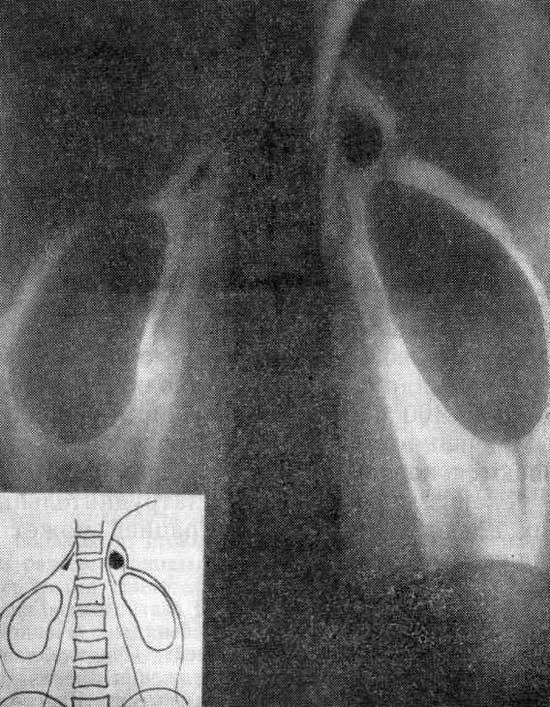

Гиперальдостеронизм (рентгенограмма в условиях пневморетроперитонеума)